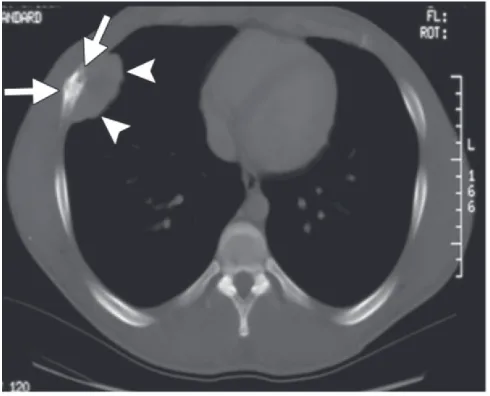

隣市の整形外科クリニックから, 肋骨腫瘍の若年成人の方が紹介されて来院されました.

持参されたCTでは, 骨が虫喰い状に破壊されており, ユーイング肉腫(Ewing sarcoma)など悪性骨腫瘍が疑われる所見. 造影MRIを急遽オーダーしました.

肋骨の内側と外側に腫瘤の形成が認められます.

引用元:Salimbene O. Primary chest wall Ewing sarcoma: Treatment and long-term results. Life 2024. 14.

最後に肋骨腫瘍の若年患者さんの造影MRIを確認. 骨内から骨外へ進展する腫瘍を認め, ユーイング肉腫を強く疑いました. 大学病院整形外科での診察を手配しました.